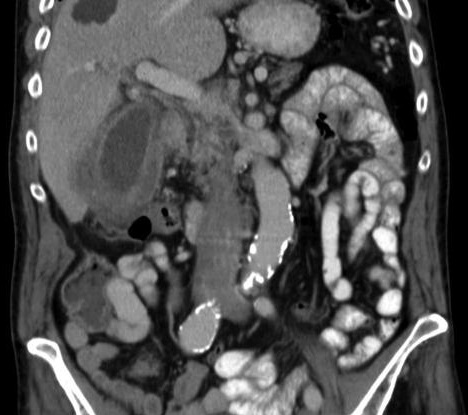

Epaissisement locale et

irregulier pseudotumorale de la paroi vesiculaire .

Image TDM en coupe axiale |

Epaississement irreguliee de

la paroi vesiculaire et images de detachement

intraluminal de la muquese vesiculaire . Oedeme et

epanchement perivesiculaire est en vue |